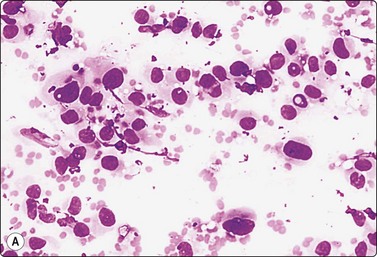

Adenocarcinoma of prostate (Figs 13.5-13.8)4,5,27,34,36,37,39

image image image

Fig. 13.5 Well-differentiated adenocarcinoma

Cohesive sheets of atypical glandular epithelium; mild nuclear enlargement and anisokaryosis; crowding of nuclei; absence of cytoplasmic granules. Note microacinar pattern in B and prominent nucleoli and a mitotic figure in C (A and B, DQ; C, Pap, HP).

Criteria for diagnosis

Cell-rich smears (if derived from a solid carcinoma nodule),

Decreased cell cohesion, variable numbers of single cells,

Three-dimensional clusters, microacini,

Interconnected large mono- or bilayered sheets with honeycomb pattern (well-differentiated carcinoma),

Indistinct cell membranes; high N : C ratio,

Nuclear and nucleolar enlargement; variable pleomorphism,

Intracytoplasmic granules only rarely present,

Positive staining for PSA and/or PSAP, absence of cytokeratin-positive basal cells.

In smears of prostatic carcinoma, sheets of benign glandular epithelial cells are commonly seen side-by-side with aggregates of malignant cells (Fig. 13.6), reflecting the diffusely infiltrative growth of the tumor. Benign and malignant cells can be directly compared (very helpful clue) and differences in cytoarchitectural features are easily appreciated. Nuclear enlargement is one of the most important criteria of malignancy. Nucleolar enlargement is better demonstrated in Pap-stained smears.

Absence of visible cell membranes, nuclear crowding and overlapping and dissociation of cells are other important criteria. The presence of coarse intracytoplasmic secretory granules makes malignancy unlikely, but they can occasionally be found in cells from well-differentiated adenocarcinoma. Cytoplasmic vacuolation may be seen in both benign and malignant cells. Nuclear pleomorphism and chromatin abnormalities are obvious in less well-differentiated cancers but may be subtle in well-differentiated carcinomas, rendering a definitive malignant diagnosis difficult (Fig. 13.5). Demonstration of basal epithelial cells by immunocytochemistry may be of help in the distinction between well-differentiated adenocarcinoma and adenosis or basal cell hyperplasia,5 but interpretation is more difficult than in histologic sections. Immunostaining is a useful tool for the diagnosis of prostate cancer at metastatic sites.42 Results may be conflicting in metastases of poorly differentiated carcinomas.

Well-differentiated carcinoma (Fig. 13.5)

Malignant microacini: abundant ill-defined cytoplasm occupying the central zone encircled by a crown of nuclei. Microacini vary noticeably in size and shape. The high frequency of microacini is one of the most important diagnostic criteria,36

Mono- and bilayered large interconnected strands of epithelium,

Few single cells,

Mild anisonucleosis,

Mild hyperchromasia,

Mild or even absent nuclear atypia,

Inconspicuous nucleoli (Pap enhances nucleoli).